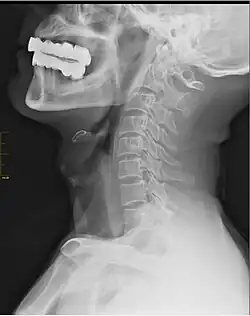

In human anatomy, arcuate foramen, also known as ponticulus posticus (Latin for "little posterior bridge") or Kimmerle's anomaly,[1] refers to a bony bridge on the atlas (C1 vertebra) that covers the groove for the vertebral artery. It is a common anatomical variation and estimated to occur in approximately 3-15% of the population.[2][3][4] It occurs in females more commonly than males.[3][5] The ponticulus posticus is created through ossification of the posterior atlantooccipital ligament.